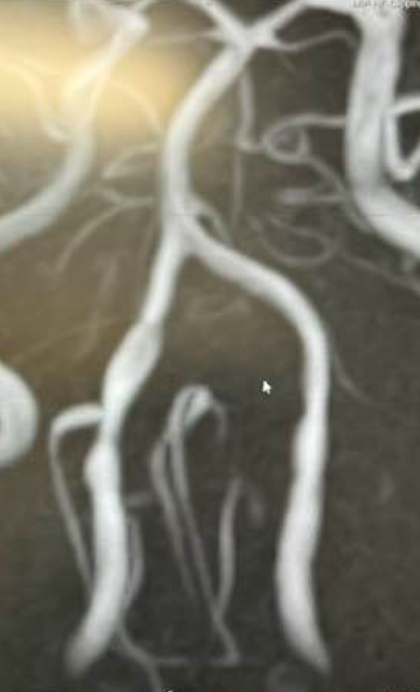

椎骨動脈解離

動脈は内膜、中膜、外膜と3層構造になっていますが、外傷や高血圧などなんらかの原因で、脳血管(脳動脈)の内膜層が剥がれてしまいそこに血流が入り込む事で、血管膨れて動脈瘤を形成し、脳出血やくも膜下出血を起こしたり、血管が閉塞して脳梗塞を引き起こしてしまう病気です。若年〜中年者の方に多く見られ、危険因子は高血圧、喫煙習慣などが挙げられます。日本人では、脳幹や小脳に灌流する椎骨動脈という重要な血管に起こる事が圧倒的に多いです。椎骨動脈解離は、後頭部に起きる突然の強い頭痛で発症します。この病気の怖い点は、くも膜下出血や脳梗塞を起こしていなくても椎骨動脈が解離する事による血管痛のみで強い頭痛を自覚します。そのため、神経症状を合併してない頭痛のみの時は、CT検査で脳卒中を否定しても、MRIなどで脳血管の評価をしなければ見落としてしまう可能性があります。治療法は入院をしてカテーテルや開頭手術になりますが、頭痛のみの症状でくも膜下出血や脳梗塞を起こしていなければ、血圧管理のみで経過を見ることがありますが、頻回なMRI検査による解離血管に変化がないか確認する必要があります。診断、治療が遅れると生命の危機に直面する非常に怖い病気の1つです。